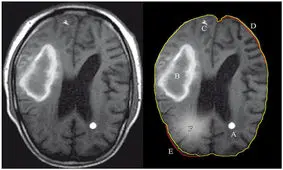

متخصصان نرورادیولژی هیأت بورد رادیولوژی وزارت بهداشت در پاسخ به استعلام ریاست سازمان نظام پزشکی درباره تصاویر «سی تی اسکن» منتشر شده از مرحوم مهسا امینی با انتشار بیانیهای اعلام کردند که «هیچ شواهدی از خونریزی مغزی در این تصاویر به چشم نمیخورد.»